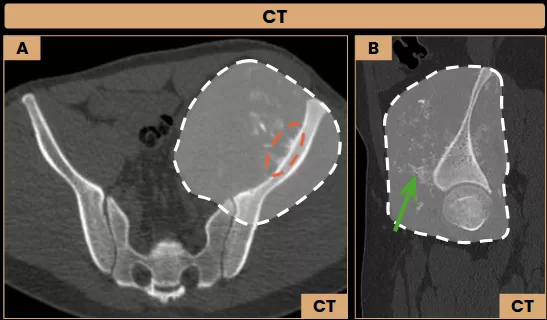

Images A and B: Axial and sagittal CT images (bone window) show a heterogeneous lesion centered on the left iliac wing, with an extensive soft tissue component (dashed line). The lesion presents interspersed calcifications/ossifications (arrow – green) and a sunburst periosteal reaction (dashed ellipse).

Image C: Axial MRI shows a necrotic area (arrow – blue) within the soft tissue component of the lesion, which also infiltrates the iliopsoas and gluteus minimus muscles (arrows – orange).